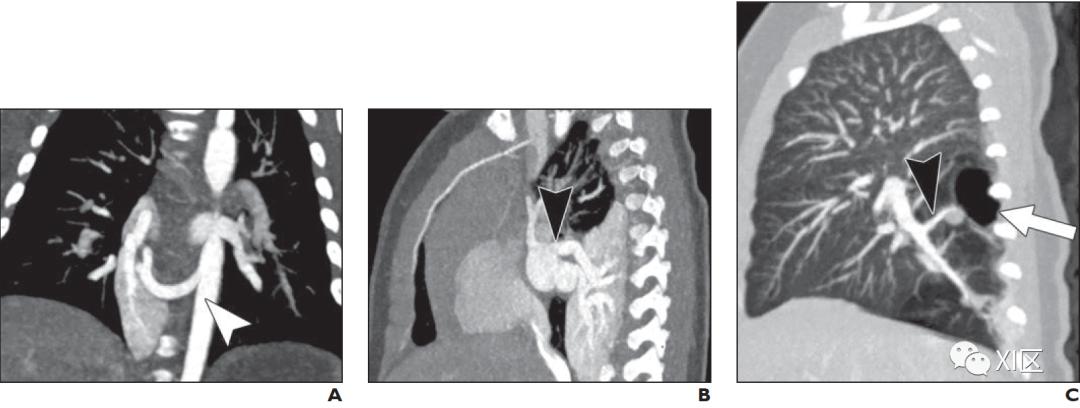

动脉期CTA的轴位成像是描述CPAM和BPS以及手术计划的首选方法(图1)。CTA很容易显示肺的异常部分,包括任何肉眼可见的囊肿。CTA显示供血动脉的位置;通过适当的CTA给药时间,还可以进一步确定静脉引流情况。虽然产后超声可以成功地识别供血动脉,但它高度依赖于操作者,在解剖定位和特征描述方面不如CT。传统导管血管造影曾经是金标准,但由于其具有侵袭性,现在很少使用。

BPS不连接气管支气管树或肺动脉。BPS分为叶内型和叶外型。叶内BPS与其余正常肺共用胸膜,通常由肺静脉系统排出,而叶外BPS有一个单独的内脏胸膜,由体静脉系统排出,通常进入奇静脉或门静脉。在CT上很难分辨出胸膜。然而,这两种类型的BPS的血管供应来自体循环,通常是降主动脉或腹主动脉,尽管在大约15%的病例中,较小的体动脉可能供应BPS。值得注意的是,在大约10%的病例中,叶外BPS可能发生在膈下;因此,扩大视野以包括上腹部很重要。

CPAM,以前被称为囊性先天性腺瘤样畸形,是一组不同类型的囊性和非囊性错构瘤性肺肿块,由发育异常的远端支气管肺泡结构组成。病变可能很小,局限于单个肺叶,可能与相邻的肺叶交叉,或是多灶性病变。CPAM与气管支气管树相通,显示肺动脉和肺静脉循环。